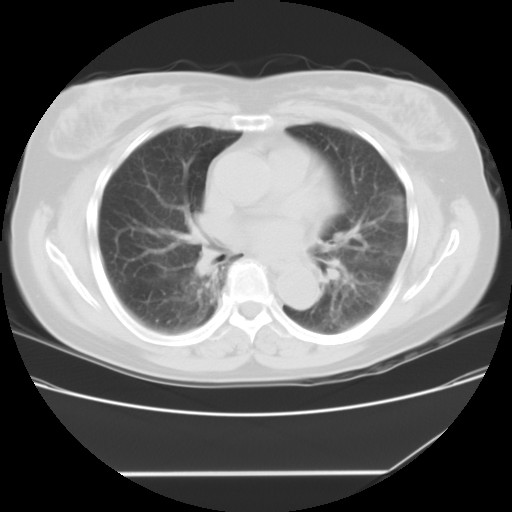

标题: CT24018:女性,62岁,咳嗽4年,无热,胸部CT扫 [打印本页]

女性,62岁,长期咳嗽,既往从事工作有粉尘接触,有高血压病史,110/150mmhg,近日咳嗽加重,脸面浮肿,请大家帮看下,

1、尘肺;2、慢性支气管炎合并肺部感染;3、心影增大(左房、左室大),考虑高血压性心脏病。

慢支并肺部炎症;右肺结核球?主肺动脉、右肺动脉影不宽,右心室不大,不支持肺心病;无心包积液。

间质性肺炎,有纤维化趋势。

1)慢性支气管炎并肺部感染、肺气肿。2)肺间质纤维化。

间质性肺炎,左下肺机化性肺炎。